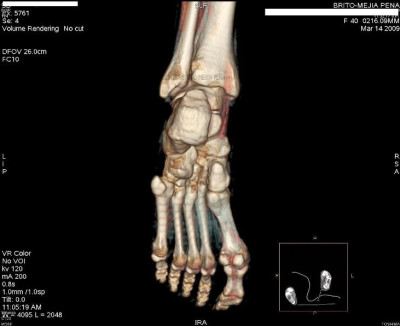

Pié normal anterior